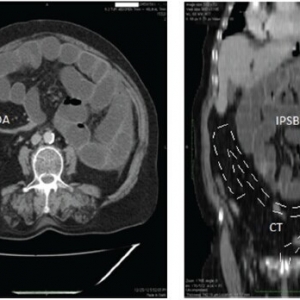

案例:腹腔动脉自发性分离解剖的形态学

形态学发现和治疗的腹腔动脉(SIDCA)自发隔离夹层。在本回顾性研究中纳入2009年1 ...